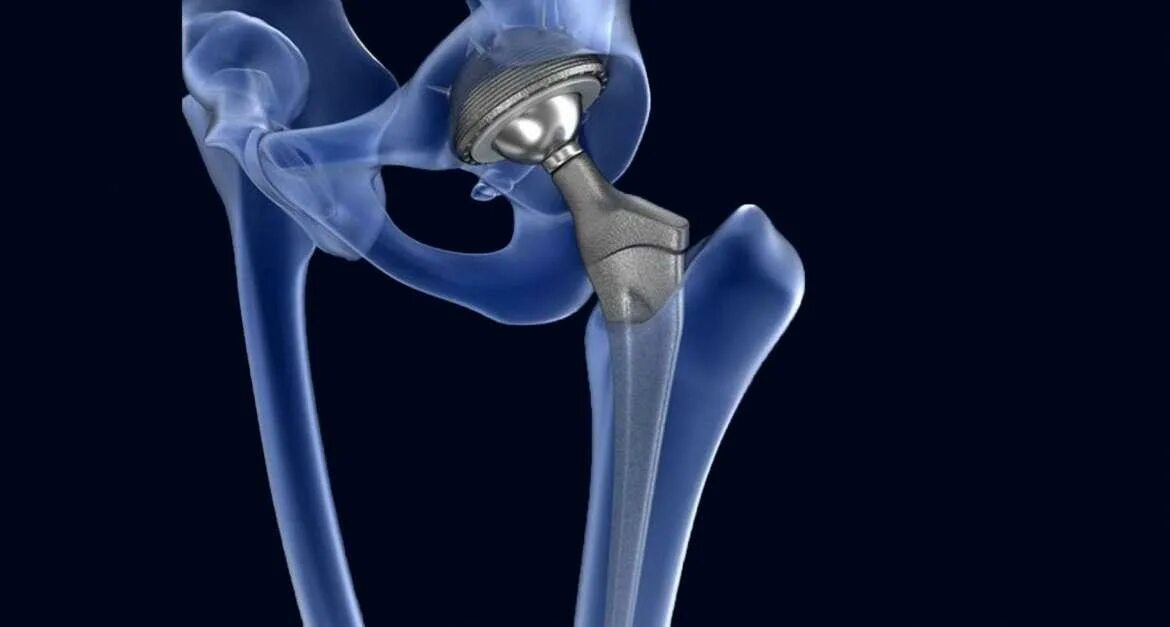

Эндопротезирование тазобедренного сустава видео